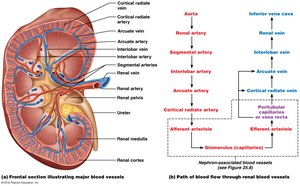

Gross Structure and Blood Flow

Blood Supply: Kidneys are highly vascularized, receiving about 20% of cardiac output.

Renal Corpuscle: Includes the glomerulus (fenestrated capillary bed) and Bowman’s capsule (with podocytes forming filtration slits).

Renal Tubules: Proximal convoluted tubule (PCT), loop of Henle, distal convoluted tubule (DCT), and collecting duct.

The JGA is a specialized structure where the distal tubule contacts the afferent arteriole. It regulates blood pressure and filtration rate.

Granular (JG) Cells: Detect blood pressure changes and release renin when BP is low.

Macula Densa: Detects filtrate osmolarity and signals adjustments in arteriole diameter.

Mesangial Cells: Release paracrine signals to regulate glomerular filtration.